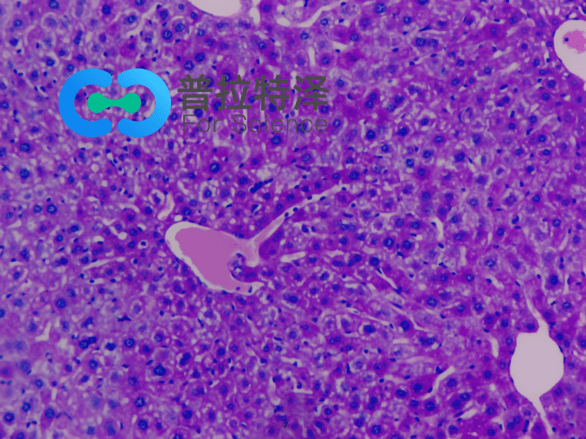

PAS染色實驗過程中常見問題解答由普拉特澤生物為大家總結分享。PAS染色作為一種在組織學中廣泛應用的染色技術,雖然具有高度的特異性和敏感性,但在實際操作過程中,也常會遇到一些問題和挑戰。本文是關于PAS染色實驗的最后一篇介紹,前面我們學習了PAS染色實驗材料有哪些?、PAS染色和mpo染色區別是什么?、PAS染色實驗注意事項以及PAS染色臨床應用,可以點擊標題直接傳送回去學習的哦。普拉特澤生物組織染色檢測平臺承接酵母雙雜實驗外包上百例,早就為大家把實驗過程中要踩的雷、吃的虧幫大家吃完了,現在我們就來看看,PAS染色中常見問題的解答:

綜上所述,PAS染色雖然是一種常用的組織學染色方法,但在實際操作中常常會遇到一些問題。通過掌握常見問題及其解決方法,我們可以更好地應用這項技術,提高染色效果和觀察結果的準確性。同時,不斷學習和實踐也是提高PAS染色技術水平的重要途徑。